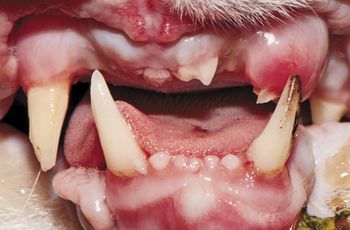

This veterinary dental condition, also called kissing lesions, can be extremely painful in affected pets and requires immediate and dedicated care.